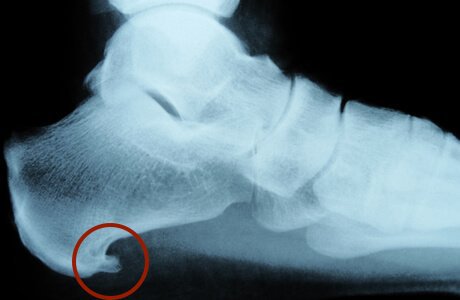

Fersensporn

Fersensporne kommen viel häufiger vor, als sie Beschwerden machen. 10-15 % aller Menschen in Deutschland haben im Laufe Ihres Lebens Beschwerden meist zwischen 40-60 Jahren, die als Fersensporn klassifiziert werden.